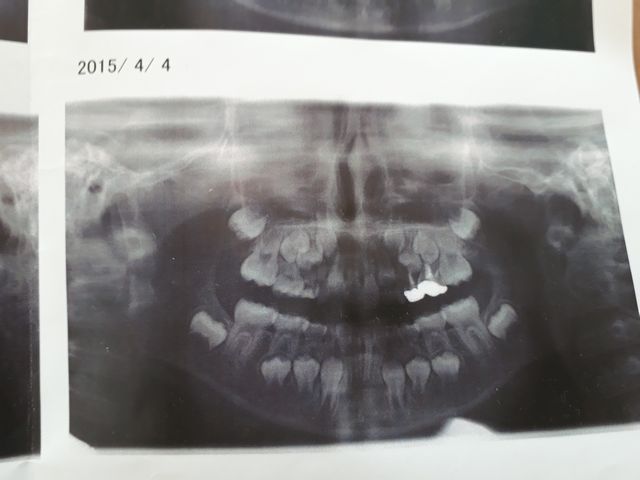

《いぬ》の矯正歯科に行きました。ヘッドギアを使い永久歯が生えるスペースを確保しました。